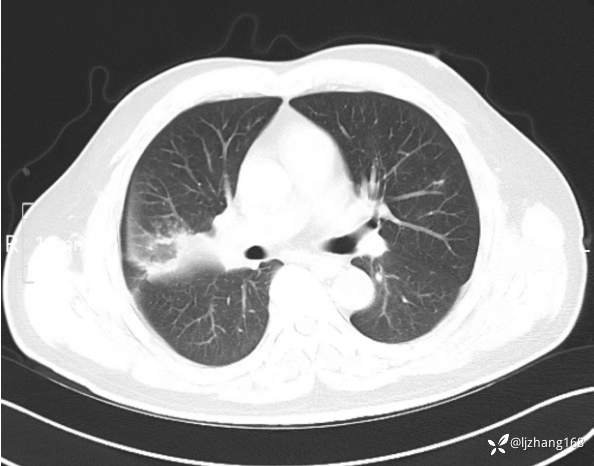

中年男患,右肺团片影,炎症0R肿瘤?

辅助检查:糖化血红蛋白12.3%。肺炎支原体IgG、IgM、呼吸道合胞病毒均未见明显异常。胸部CT:右肺上叶阻塞性肺炎。